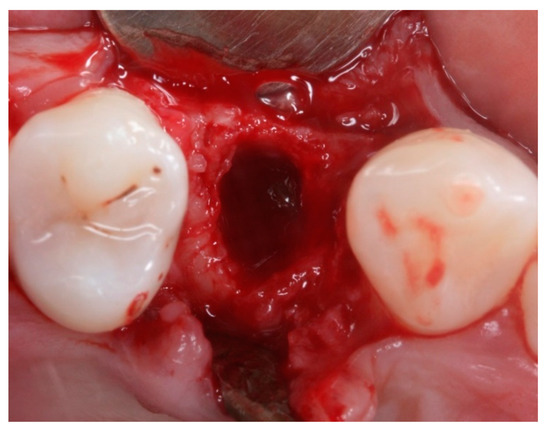

2. Materials and Methods

2.4. Groups

2.5. Post-Surgical Procedures